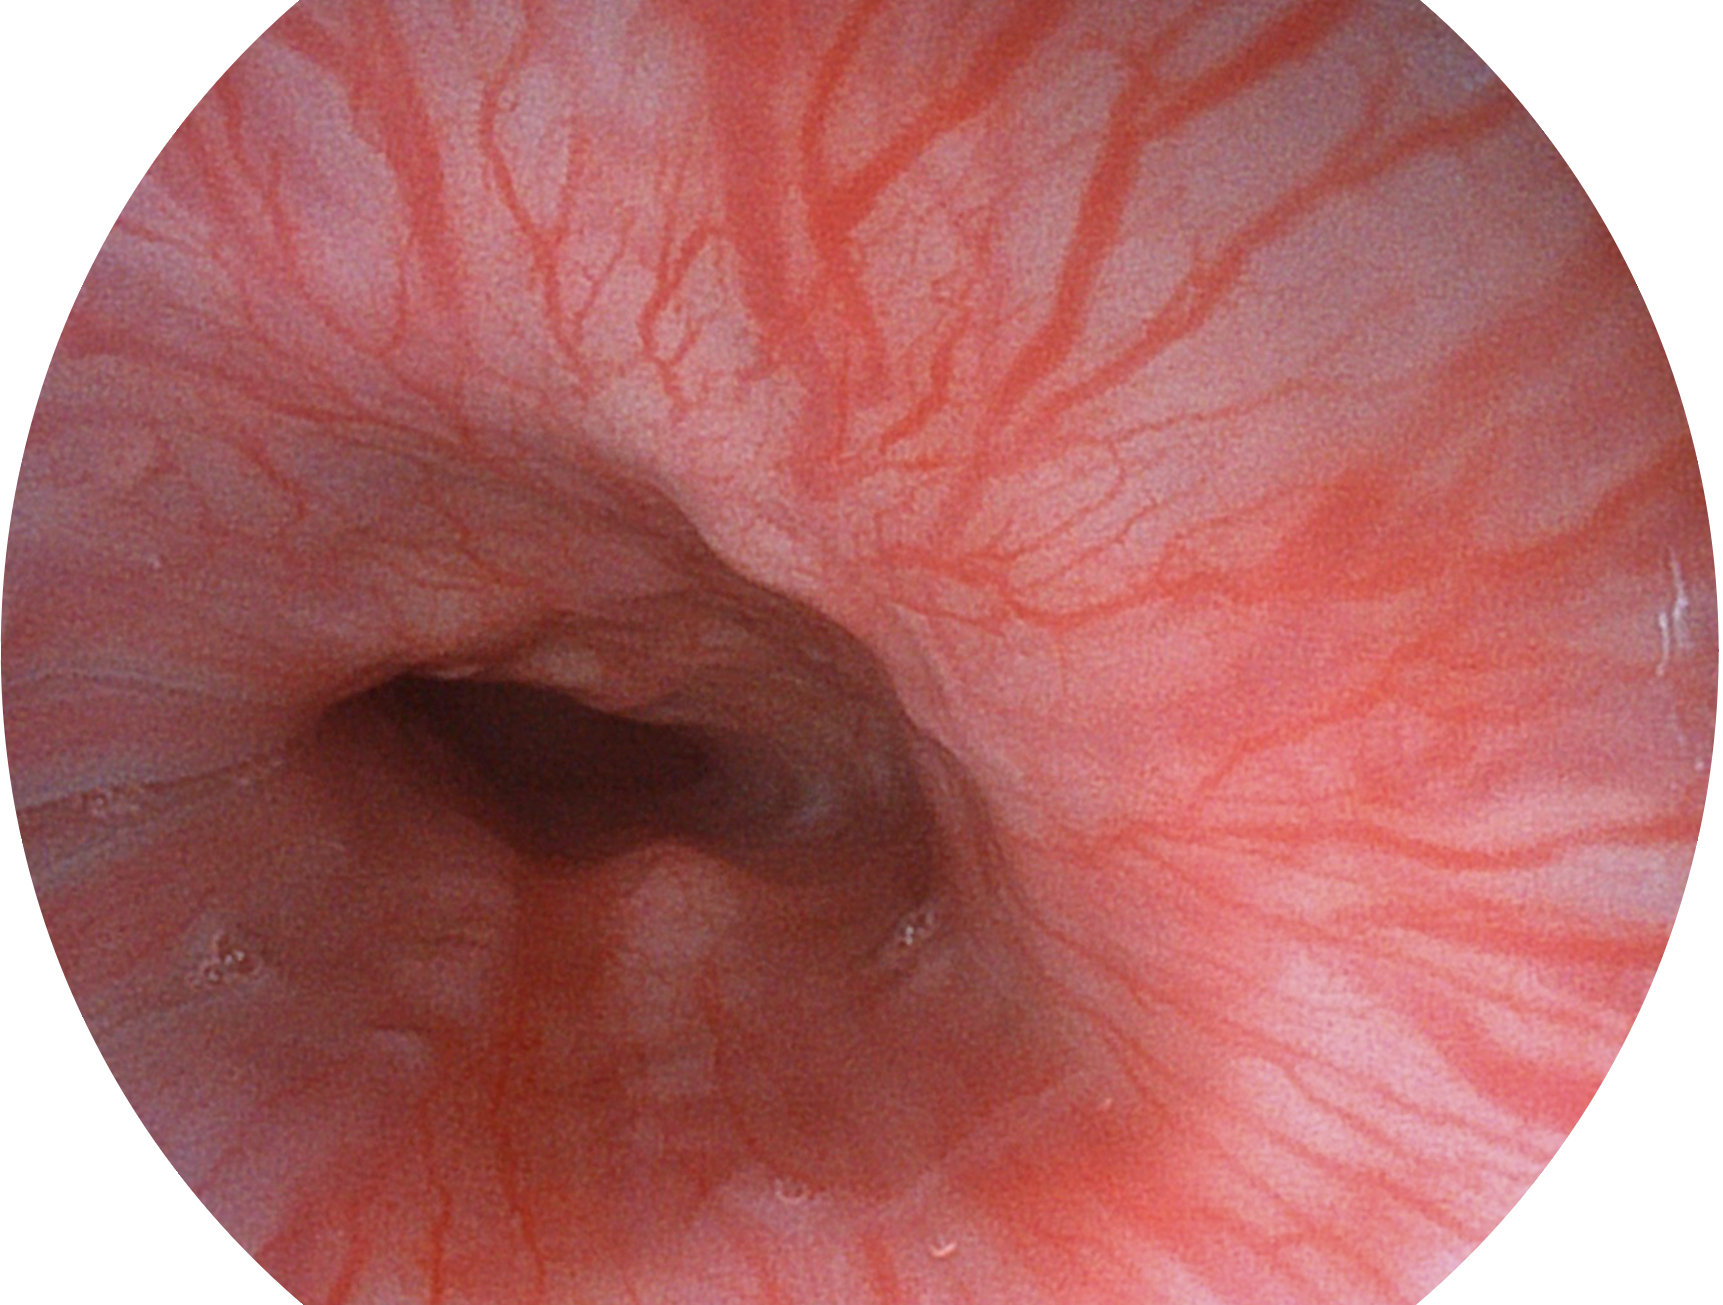

银河集团官网新开发的内镜染色技术,主要是基于多波长LED 光源的开发,VLS-55Q 四波长LED 光源是由四个不同颜色的LED光按照相应照明模式所规定的特定发光比例进行合束后形成,合束后形成的照明光的光谱由红光、绿光、蓝光及蓝紫光这四个不同的波段范围构成。具有更高光谱自由度,通过光谱比例的控制,实现了聚谱成像技术,英文全称为“Spectral Focused Imaging, SFI”,缩写为“SFI”和光电复合染色成像技术,英文全称为“Versatile Intelligent Staining Technology, VIST”,缩写为“VIST”。